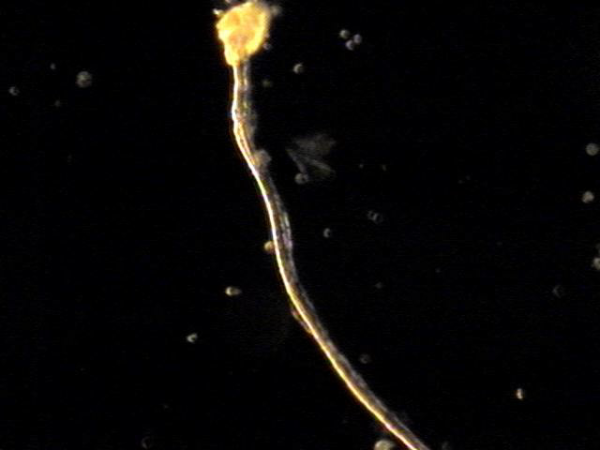

주 2회 전립선과 정낭 그리고 정관등의 표적 치료중 정관을 막고 있는 거짓중층원주상피세포와 사정되지 못한 정자들과 단백질등의 치료된 현미경학적 자료입니다.

This microscopic image was taken after repeated targeted treatment.

It shows that old cells, proteins, and sperm had collected and blocked the vas deferens.

The size of this material confirms that it was stuck inside the vas deferens.

The treatment helped to remove this blockage, allowing the ducts to open and improving the flow of semen.

사진 속 현미경 영상은 정관에서 배출된 치료 후 내용물로 보입니다. 관찰되는 소견을 근거로 말씀드리면:

-

길게 뻗은 섬유성 구조와 세포성 잔여물이 함께 보입니다.

이는 흔히 노화된 거짓중층원주상피세포, 단백질 덩어리, 또는 정자와 점액질이 엉겨 붙은 물질일 가능성이 높습니다.

직경이 비교적 크고 길게 뭉친 형태를 띠기 때문에, 정관 내강을 막아 정액의 흐름을 방해했을 것으로 추정됩니다.

즉, 정관을 막고 있던 주된 원인은

오래된 상피세포 찌꺼기, 단백질 응집물, 그리고 사정되지 못하고 고여 있던 정자들이 엉겨 형성된 덩어리(blockage material) 로 보입니다.

This microscopic image shows material that was removed after targeted treatment of the vas deferens.

The findings suggest that the blockage was mainly caused by:

- Old cells that had shed from the lining,

- Protein debris, and

- Sperm that could not be released and became trapped.

These substances clumped together over time and formed a plug large enough to block the vas deferens, preventing normal flow.

The treatment helped clear this material, allowing for better passage through the duct.